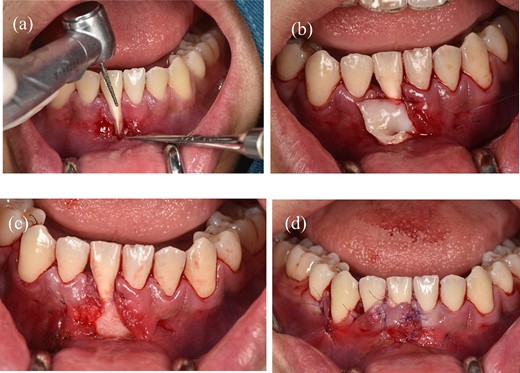

Before surgery: scaled the lower incisors and endodontic treatment. After 2 weeks, the inflammation of the gingival had decreased and we can start the gingival graft treatment and the surgical procedure is depicted below (Fig. 3). Local anesthesia then followed by meticulous preparation of the tooth surface using a high-speed handpiece. To prepare the root surface, a 24% ethylenediaminetetraacetic acid (EDTA) gel was used. To obtain an epithelialized connective tissue graft (CTG), tissue was harvested from the hard palate in the area from first premolar to first molar. The graft was carefully shaped and sized based on the specific measurements of the gingival recession defect. A specialized 15C blade was utilized for this precise procedure. Subsequently, a thin layer of epithelial tissue, ~0.5–1 mm in thickness, was eliminated from the graft using a high-speed handpiece and 2 mm round diamond bur, except for the specified epithelial section as illustrated in (Fig. 2a). A piece of connective tissue in size 13 × 13 × 1.5 mm was harvested to adequately cover the entire tooth root (Fig. 2b and c). Afterward, Emdogain was applied to the complete root surface, starting from the most apical bone level to maximize the therapeutic potential of Emdogain in facilitating tissue regeneration and promoting periodontal healing. On the right side, where gingival recession was observed on the teeth, a flap with varying thickness was raised. This flap featured a split-thickness technique in the papillae and vestibular sulcus, while maintaining full thickness at the center. An incision was created to alleviate tension, specifically at a location distant to the right canine. Through the sulcular access on the left side of tooth 41, the graft was inserted into the tunnel, and the epithelial segment of the graft was positioned over the exposed root. Subsequently, the graft sites on both the left and right central incisors were secured using 6–0 monofilament sutures. Finally, the gingival flap was repositioned to cover the entire connective tissue area (Fig. 4). Subsequent assessments and recording of the healing process were performed at intervals of 3 weeks, 2 months, 6 months, and 1 year through reevaluation and imaging (Figs 5 and 6).

(a) The process of deepithelialization at the hard palate involves the utilization of a high-speed handpiece. (b) The thickness of a subepithelial connective tissue graft. (c) The dimensions of a subepithelial connective tissue graft.

Illustrative depiction of the surgical procedure (a) Initial condition. (b) Flap design in the recipient area: yellow area represents tunnel incision, blue area represents split-thickness flap, and green area represents full-thickness flap. (c) Full-thickness flap. (d) Stabilize the connective tissue graft. (e) Rotate the flap and reposition the gingival margin. (f) Suture the flap.

(a) Preparing the tooth surface using a high-speed handpiece. (b) Unilateral tunneling technique. (c) Stabilize the connective tissue graft. (d) Rotate the flap and reposition the gingival margin.